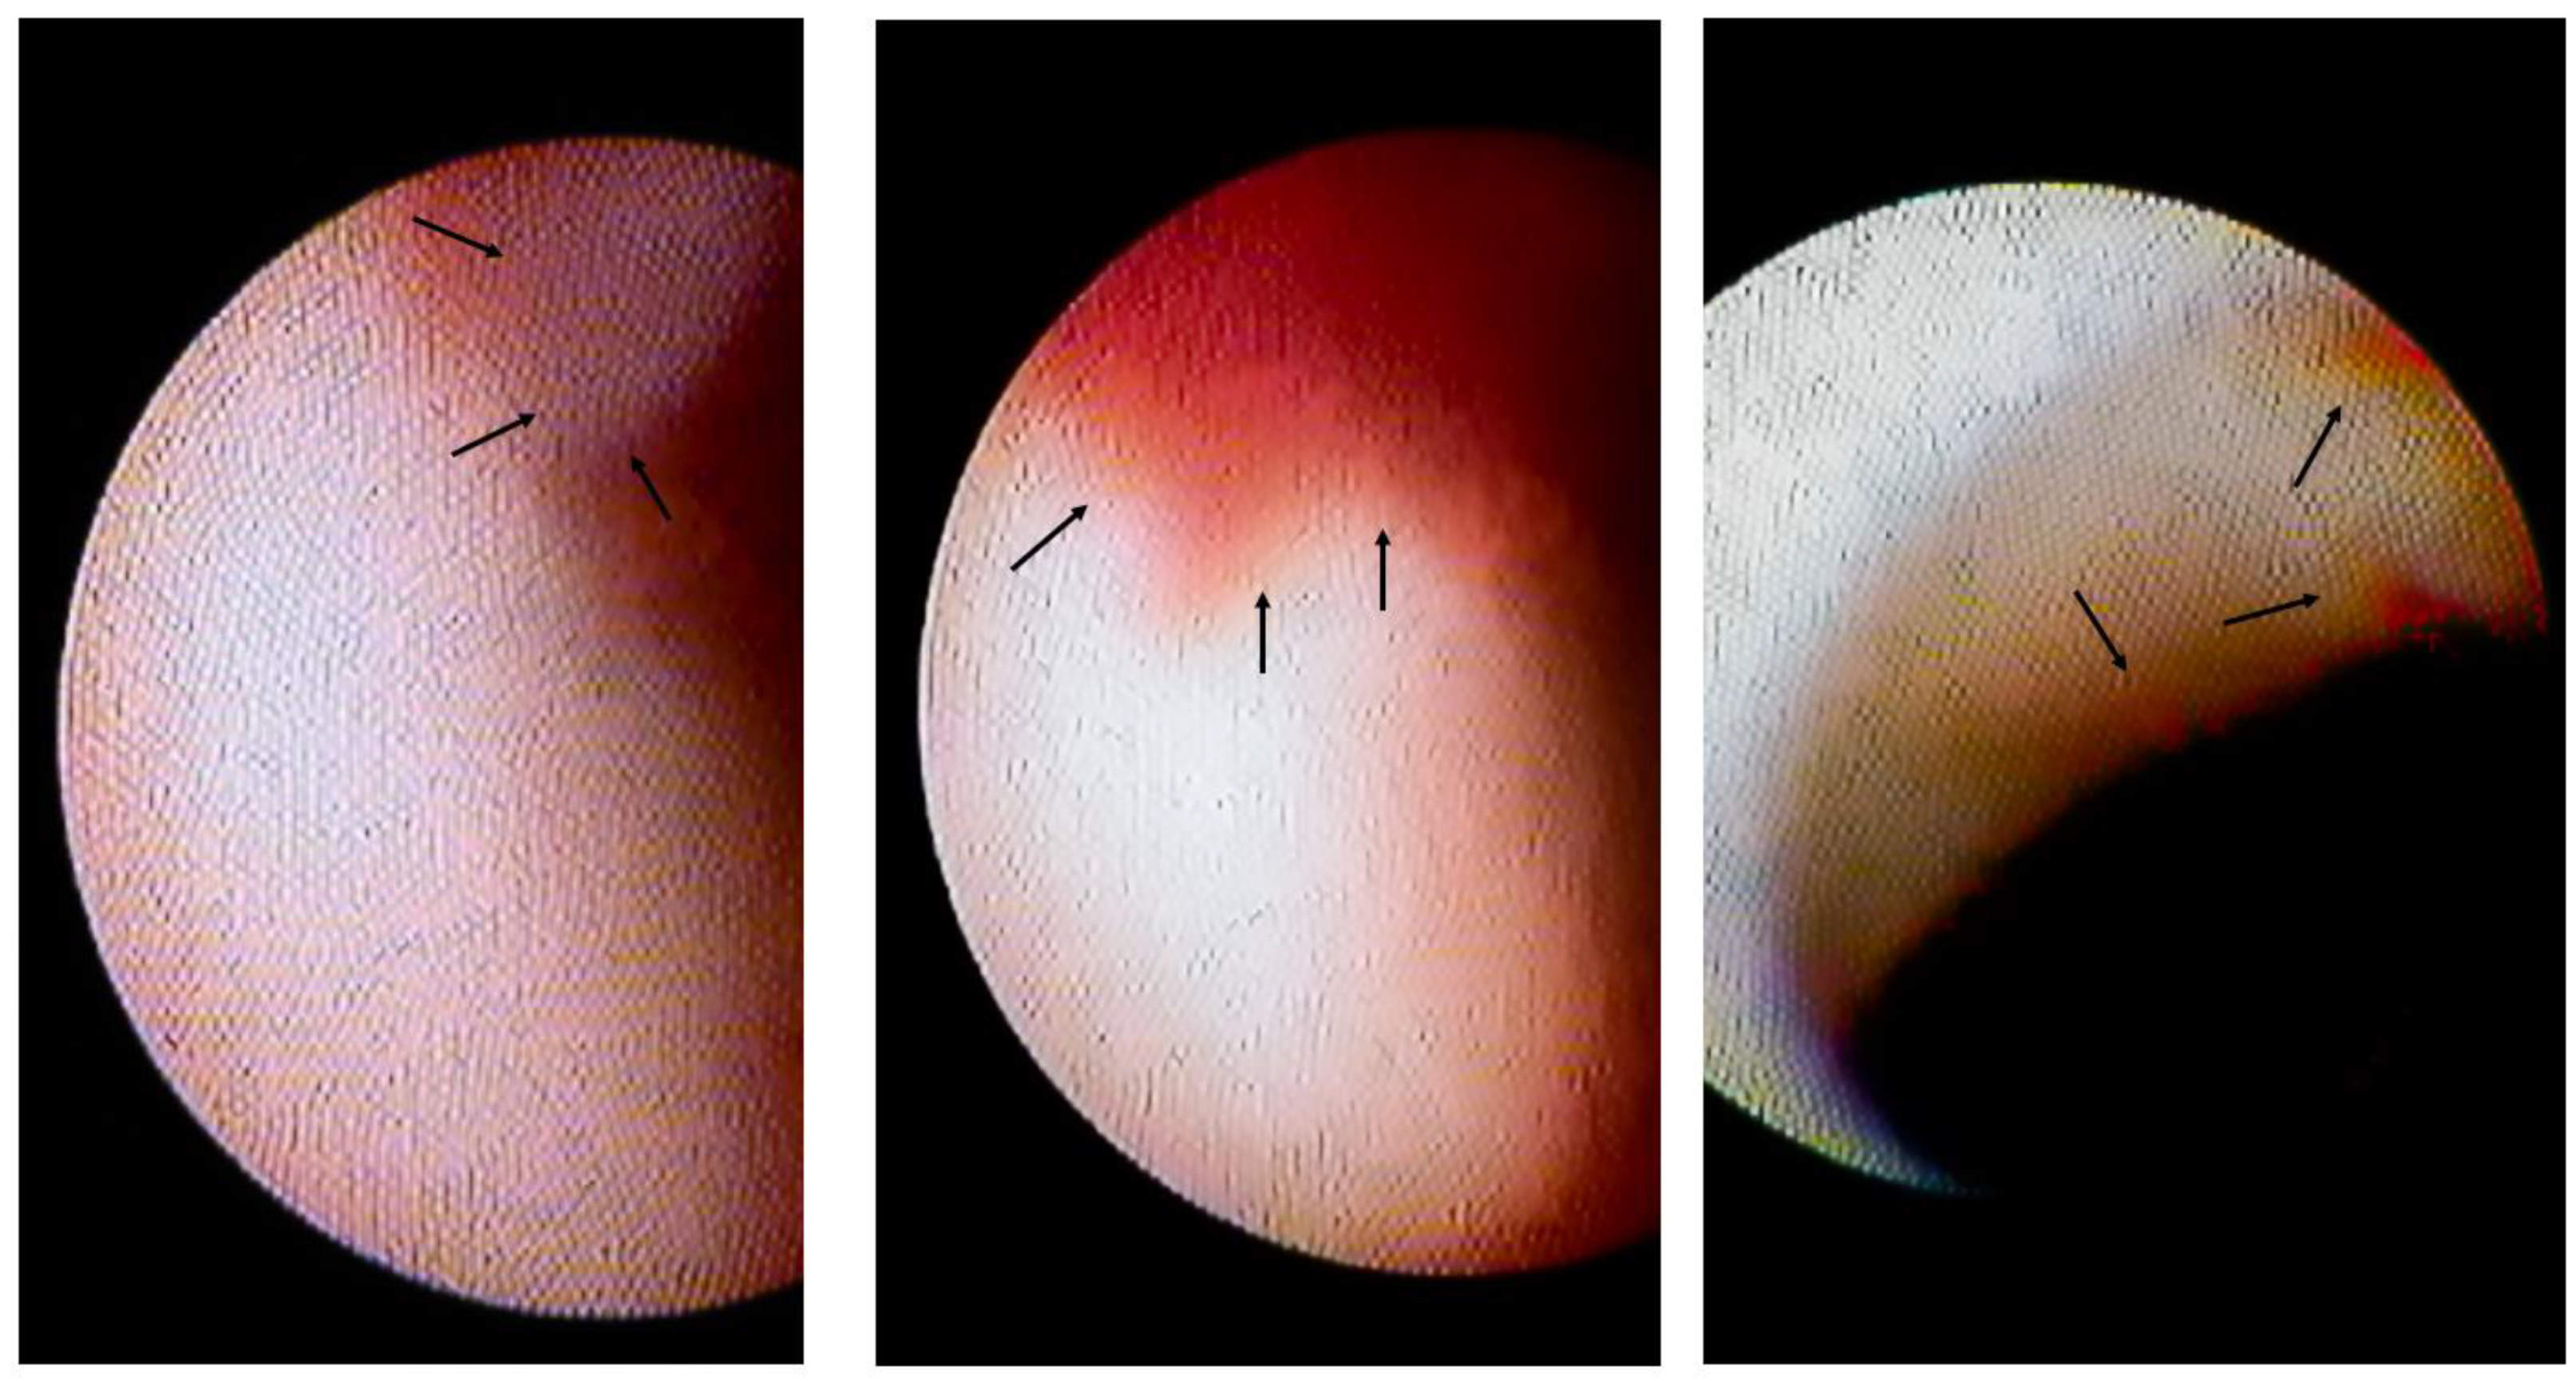

3.2. Lesion Characteristics with Intracoronary Thrombi

| Intracoronary Thrombus (−) | Intracoronary Thrombus (+) | p-Value | |

|---|---|---|---|

| No. | 52 | 18 | |

| LAD/LCX/RCA | 38/3/ 11 | 13/2/3 | 0.72 |

| Atherosclerotic change on coronary angiogram (%) | 9 (17) | 11 (61) | <0.01 |

| Yellow plaque (%) | 41 (71) | 15 (83) | 0.68 |

| Degree of yellow plaque | 1 (1, 2) | 1 (1, 2) | 0.4 |

| Focal spasm (%) | 14 (27) | 11 (71) | <0.01 |

| Segmental spasm (%) | 23 (44) | 16 (90) | <0.01 |

| Total or subtotal spasm (%) | 13 (25) | 9 (50) | 0.04 |